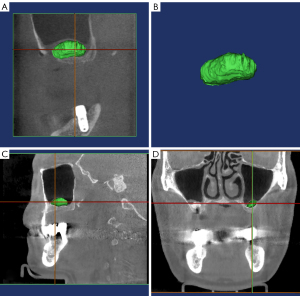

Patients were divided into 2 groups according to the experimental design: (I) LSFE with simultaneous implantation and (II) LSFE with delayed implantation. Preoperative clinical and radiological examinations were performed. Radiographic examination of the maxillary sinus of each patient was performed using CBCT before the LSFE surgery (T0), immediately after the surgery (T1), and 6 months after the surgery (T2). CBCT scans and volume measurements using Minics were performed by the same clinician for all patients. This reduced measurement errors and considerably improved reliability (Figure 1). The following materials were used: bio-absorbable collagen membrane (Heal-All®, Yantai Zhenghai Bio-tech Co., Ltd., China), Tianbo bone powder (Bio-osteon, BEIJING YHJ, Beijing), and an implant system (Straumann, Switzerland; SIC, Switzerland). Minics was used to measure the 3D data and the volume of the maxillary sinus bone graft material at T1 and T2 and analyze the results.

Minics, a representative software for manual segmentation, is one of the most commonly used software packages in clinical settings (16,17). Minics can be used for fracture reduction, orthognathic surgery, local plastic surgery, airway lesions, etc. Weissheimer et al. demonstrated several advantages in terms of imaging and highlighted the wide range of applications of the Minics software in biomedical engineering (18). Minics’ 3D reconstruction and visualization module enables the study of thin-slice CT volumetric datasets in 3 orthogonal planes (transverse, sagittal, and coronal planes), and the image visualization function provides axial, coronal, and sagittal views of the raw data with a reconstructed 3D view, including translation, scaling, and rotation. To date, few studies have been conducted on the application of Minics in measuring volume changes in the LSFE region. We used Minics to evaluate volume changes at the elevation site following LSFE.